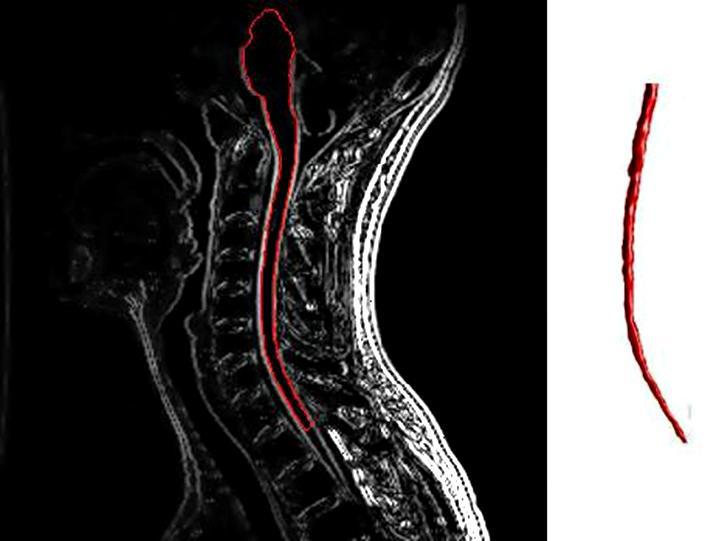

Η σκλήρυνση κατά πλάκας (ΣΚΠ) είναι μία από τις πιο συχνές παθήσεις του κεντρικού νευρικού συστήματος (εγκέφαλος και νωτιαίος μυελός) οι οποίες μπορεί να οδηγήσουν σε διάφορα νευρολογικά συμπτώματα και αναπηρίες.

Στην περίπτωση της Σκλήρυνσης κατά Πλάκας, αυτή η δυσλειτουργία του ανοσοποιητικού συστήματος καταστρέφει τη λιπαρή ουσία που καλύπτει και προστατεύει τις νευρικές ίνες στον εγκέφαλο και το νωτιαίο μυελό (μυελίνη).

Αυτό έχει ως αποτέλεσμα τη διακοπή της επικοινωνίας μεταξύ του εγκεφάλου και άλλων μερών του σώματος.